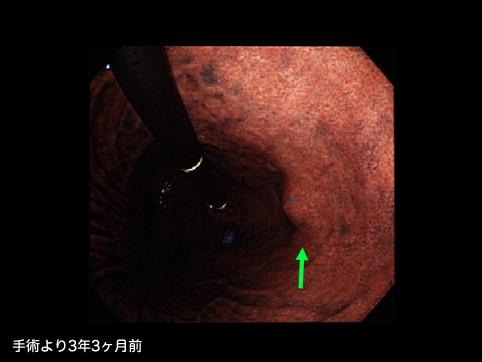

症例提示(所在地,施設名等): 福岡県・ 九州がんセンター

症例登録日 2010/01/12

画像ID:11326

疾患(病理主体)の分類悪性非上皮性腫瘍/平滑筋肉腫(含GIST)

部位(臓器別)胃(部位)/体部

検査方法内視鏡

病変の最大径(ミリ)10〜14